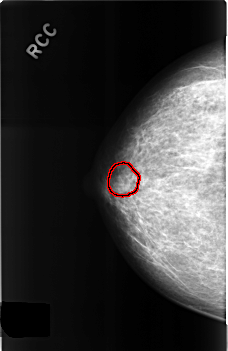

C_0311_1.RIGHT_CC

RIGHT_CC LINES 4560 PIXELS_PER_LINE 2952 BITS_PER_PIXEL 12 RESOLUTION 50 OVERLAY

FILE: C_0311_1.RIGHT_CC.OVERLAY

TOTAL_ABNORMALITIES 1

ABNORMALITY 1

LESION_TYPE MASS SHAPE OVAL MARGINS CIRCUMSCRIBED

ASSESSMENT 3

SUBTLETY 3

PATHOLOGY BENIGN

TOTAL_OUTLINES 1